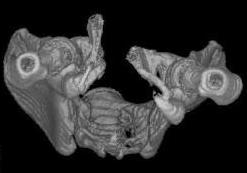

Уважаемые коллеги! Девушка 18л сросшиеся переломы лонных, седалищных костей с обеих сторон, перелом крестца справа,перелом костей голени справа (зио), 3 мес после травмы, АВФ снят с таза. Патологической подвижности нет. Стоит самостоятельно, ходит с костылями, поскольку 3 месяца практически не ходила. Беспокоит выступание лонной кости в области лобка, хотя объективно грубого косметического дефекта нет. На кт разворот лонной кости в сагиттальную плоскость. Вопрос: стоит ли добиватьсяполной репозиции или же достаточно произвести остеотомию верхушки выступающего отломка?

Предварительный диагноз- посттравматическая вертикальная нестабильная деформация таза II степени, неправильно срастающийся перелом боковой

массы крестца справа, правой лонной и седалищной костей, застарелый разрыв лонного сочленения.

Для уточнения диагноза ниеобходимы обзорные рентгенограммы таза (прямая и inlet), Кт срезы на уровне переломов для определения степени сращения и решения вопроса о методе оперативного восстановления анатомии (делать ли остеотомию, низводить ли задние отделы), ни о какой "остеотомии выступающих отломков" тем более у девочки 18 лет речи быть не может.

Предоставляю срезы. Если пациентку функционально ничего не беспокоит, стоит ли навязывать ей лечение.